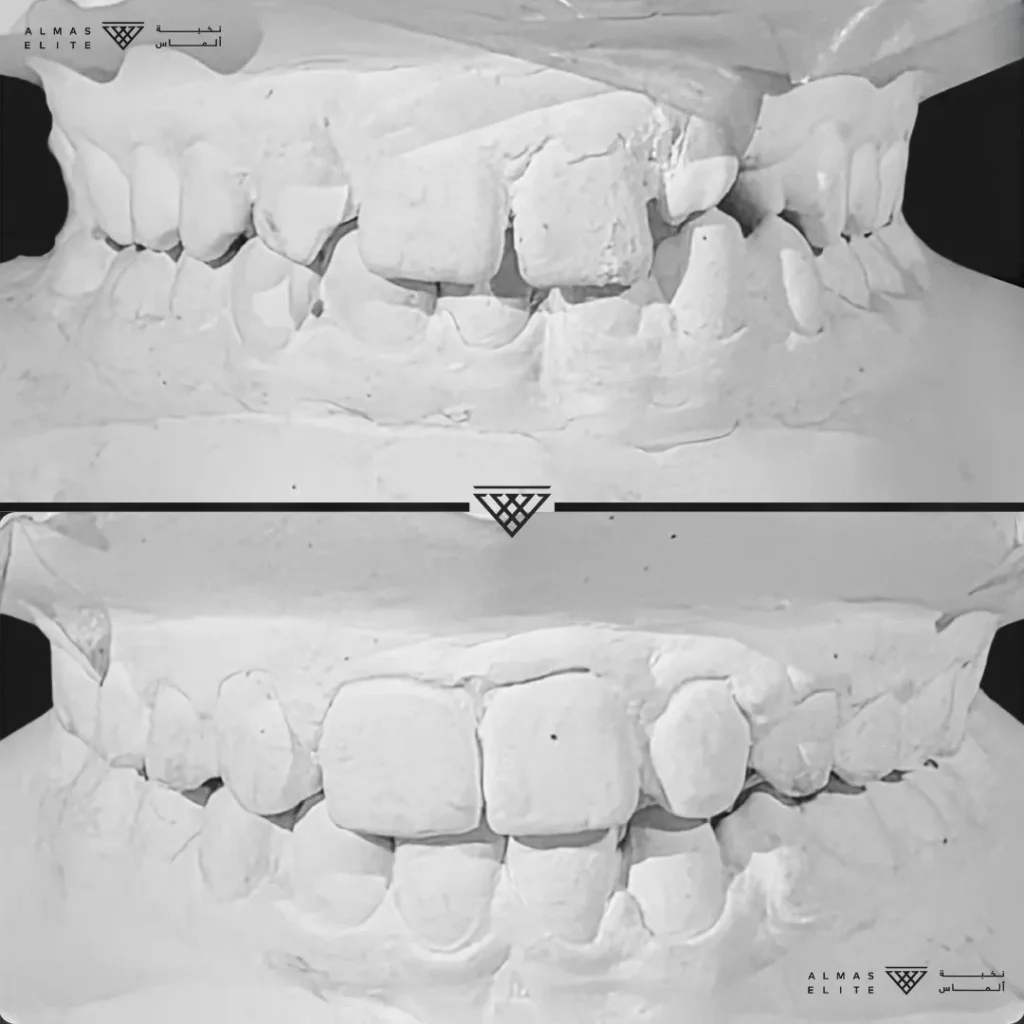

٢) التقييم والتشخيص الشامل

يشمل صور الأشعة والتحليل الرقمي للأسنان والفكين للوصول إلى تشخيص دقيق.

٣) وضع خطة علاجية مخصصة

تتضمن نوع الجهاز الأنسب، المدة المتوقعة، وتكلفة العلاج، مع شرح واضح لما يمكن توقعه أثناء رحلة التقويم.

- تشخيص دقيق يشمل الأشعة والتحليل الرقمي للأسنان والفكين.